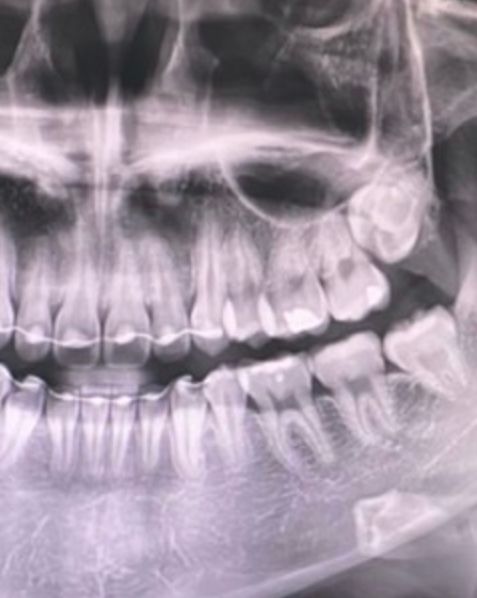

사랑니 꼭 발치해야 하나요??

아래 사랑니를 꼭 뽑아야 하는지 궁금합니다

바르게 자라는 사랑니는 아닐까요?

그리고 위사랑니를 빼면 아래도 무조건 발치해야 하나요??

위쪽 사랑니는 매복상태이신거 같습니다. 불편하시다면 발치를 하시는게 맞고, 일반적으로 위아래를 같이 뽑습니다. 아래쪽 사랑니는 잘 맹출된거 같으니 관리를 잘하신다면 발치를 안하셔도 되지만, 불편하시다면 발치를 하시는게 좋습니다.

말씀하신 것처럼 아래 사랑니는 상당히 똑바로 맹출되어 있습니다. 다만 전문가인 치과의사도 사랑니까지 완벽하게 관리하기가 쉽지 않습니다. 따라서 일반인들이 사랑니를 관리하기 힘들며 결국에는 사랑니 주변에 충치가 생길 가능성이 높습니다. 사랑니 충치는 크게 문제가 되지 않을 수 있으나 앞에 있는 어금니까지 손상될 수 있으므로 가급적이면 발치하는 것이 좋습니다.

물론 본인이 관리를 정말 잘한다면 꼭 뽑지 않아도 되는 사랑니는 맞습니다.

현재 아래사랑니에 충치나 치주질환이 있어보이진 않습니다.

현재 문제가 없다면 나중에 발치하셔도 될 것으로 보입니다. 하지만 관리가 안되고 음식물이 자주 끼며, 자주 붓고 아픈경우 발치하는게 좋습니다.

위의 사랑니를 발치한다고 해서 반드시 아래사랑니를 발치해야하는것은 아닙니다.

매복되어 있고 다른 치아에 문제를 발생시킬가능성이 없다면 발치하지 않아도 됩니다. 또한 똑바로 나와 있고 관리가 잘되고 있으며 충치나 치주질환이 없다면 그냥 사용하는경우도 있습니다.

아래 사랑니의 경우에는 위에 대합하는 치아가 없기 때문에 나중에 정출되어 위에 잇몸을 자극할수 있습니다.